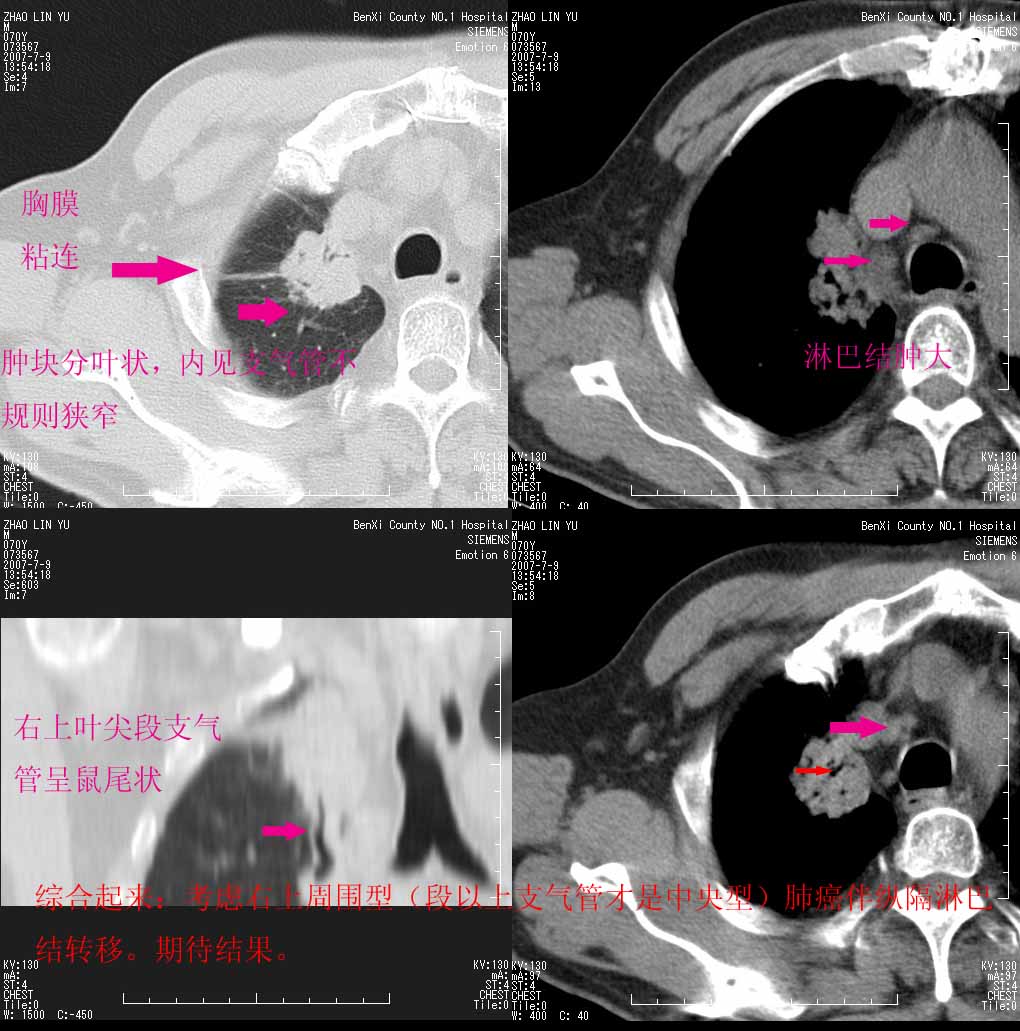

以下是引用王靖旗在2007-7-10 17:12:00的发言:[br] 男、70、咳嗽两个月,半年前换瓣手术,胸片未见异常,于昨天行x片发现右肺上野大片影,行ct扫描,这里是减薄图像,余肺正常。明天晚上会有增强扫描片,到时我会上传。[br][br] 冠状位请大家细看,应该是有意义的,[br][br] 请大家先看平扫发表意见。[br][br]

以下是引用zhangzhongshou在2007-7-10 21:43:00的发言:[br]右肺上叶周围型肺癌,以孤立型细支气管肺泡癌可能性大。